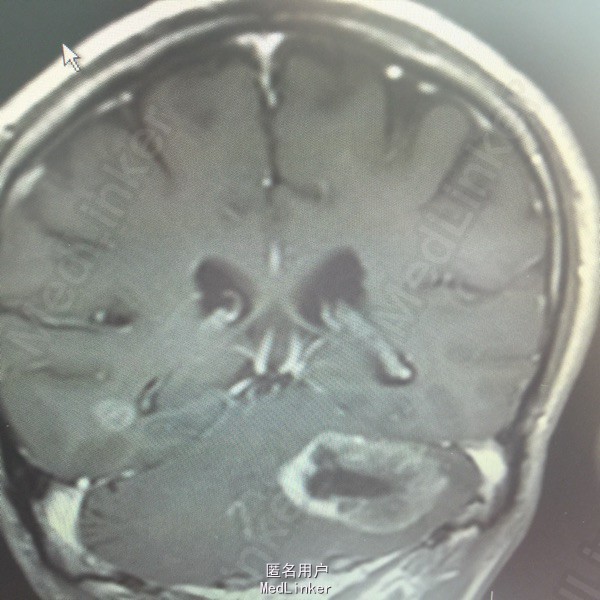

男,54岁,以头痛半个月入院。 现病史:半个月前无诱因头痛,呈胀痛,无呕吐,无意识障碍,病来咳嗽、咳痰,体重减轻约5斤,无发热。 既往史:无特殊。

查体:BP:150/100mmHg,神清语明,两瞳孔等大正圆,直径约3.0mm,光敏,四肢肌力5级,肌张力正常,腱反射艹,左侧共济运动阳性,病理征阳性,脑膜刺激征(-)。 辅查:见下:

肺癌脑转移。 影像解读(影像如何解读是临床工作中非常重要的一环)。 左侧额叶近皮质长Tl长T2信号,局部颅骨缺损,右侧枕叶不规则病灶,TlWl呈中心呈等信号,周围高信号,T2Wl呈高低混杂信号,伴大片水肿,相邻侧脑室后角、胼胝体受压。增强呈不规则环环强化。 已进行局部放疗治疗。